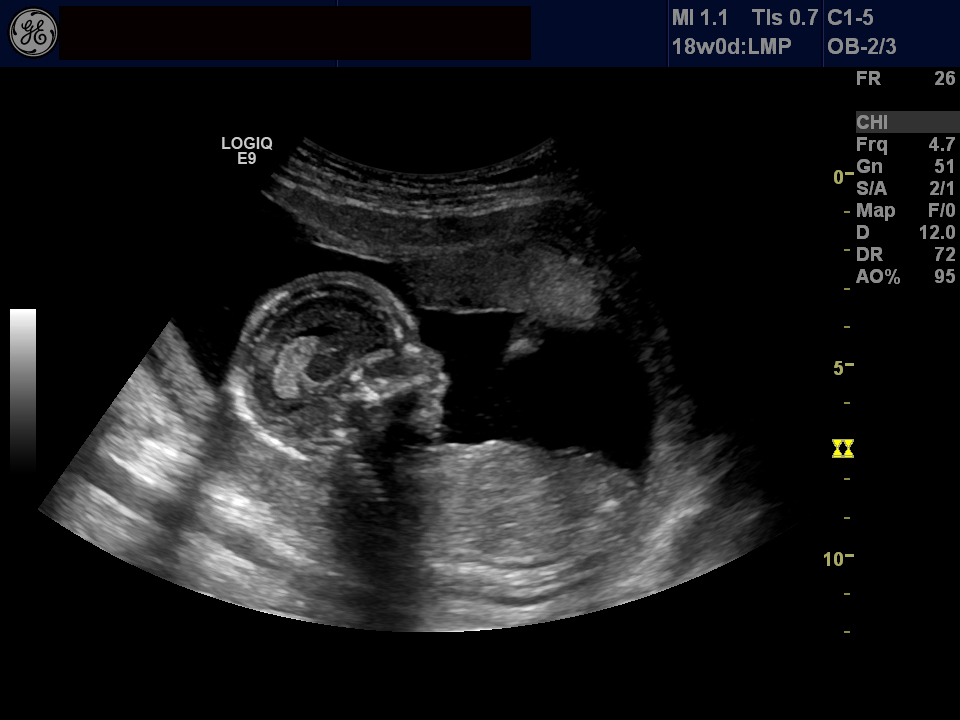

It was so much fun to see the baby! The first thing I saw were the four chambers of the heart, beating away. The heartrate was 141. The ultrasound tech went through and measured all of the parts she needed to measure. She said everything looked perfect. The nuchal fold was thin like it was supposed to be. The baby kept trying to suck his/her thumb -- how sweet! My daughter does that. After we got all of the measurements, the u/s tech switched wands and went 3D (my clinic got one of those after my last baby, so this was my first time experiencing the 3D) -- pretty neat! The placenta was in the way, so it was hard to get a good face image, but she did get a few.

He/she measured 7 oz. and right on track for 18 weeks, which keeps my due date at August 29th.

So here he/she is! Enjoy. :)